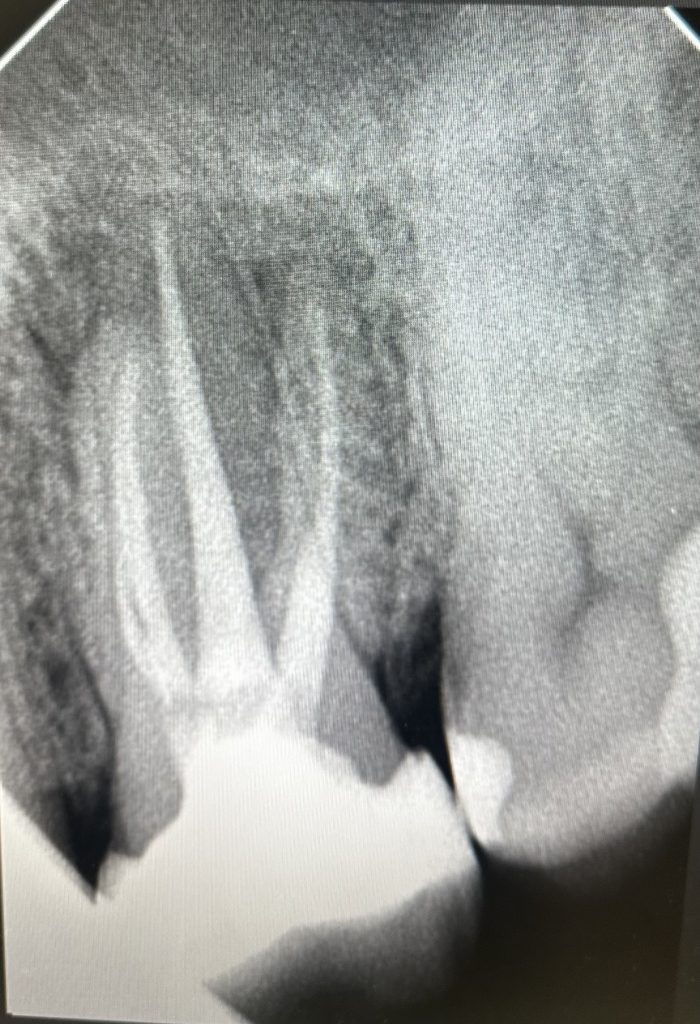

• Диагностика и лечение кариеса и его осложнений (пульпиты, периодонтиты)

• Эндодонтическое лечение корневых каналов с использованием стоматологического микроскопа